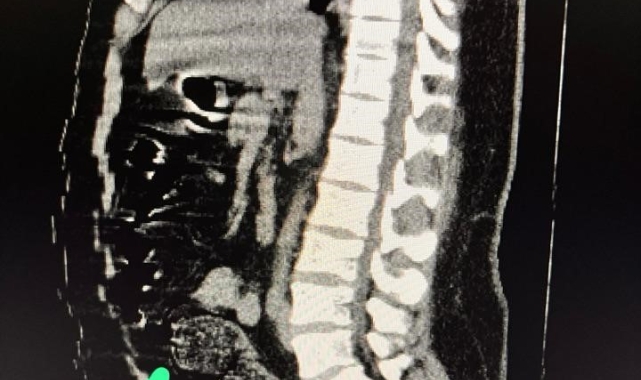

Adli makamların talimatı üzerine Gümüşhane Devlet Hastanesine götürülen şahsa yönelik iç beden muayenesinde bağırsaklarında 3 adet kapsül olduğu tespit edildi. Hastanede yapılan müdahalenin ardından şahsın bağırsaklarından çıkarılan kapsüllerin içerisinde toplamda 271,55 gram metamfetamin ele geçirildi.